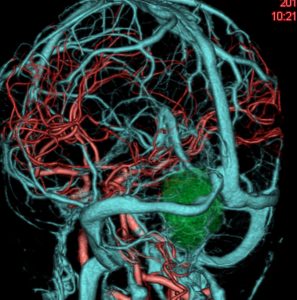

静脈洞交会髄膜腫 meningioma of the confluence of sinuses

若い女性に偶然発見されたものです。直静脈洞と静脈洞交会の接合部あたりに発生したもので,静脈洞はほぼ閉塞に近い所見でした。しかし,この部分の静脈洞は,テント硬静脈側副路が発達することがあるので,硬膜を含めた積極的な摘出をすることは絶対にできません。もしほんの少しでも流れがある直静脈洞を閉塞させると短時間に脳死になるような脳静脈圧亢進が生じる可能性があるからです。静脈洞内に少し取り残して(右下の矢印)手術を終了しました。手術後には定位放射線治療を行って再増大を防ぎます,